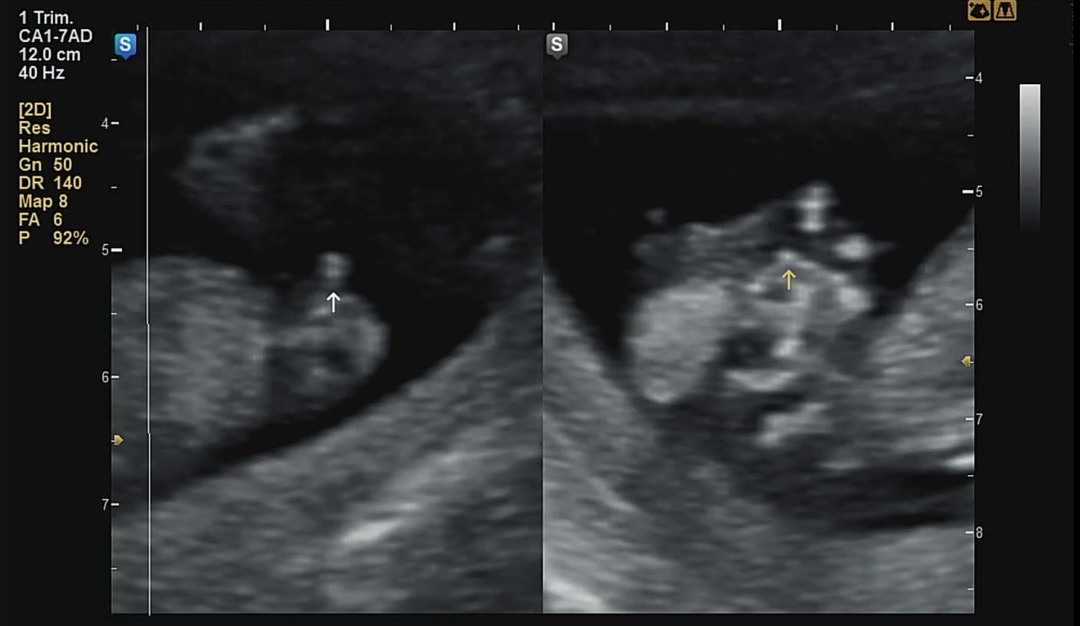

각도법 고수님들! 12주2일 초음파 봐주세요

12주 2일인데 왼쪽 캡쳐가 생식기쪽이예요,, 이건 완전히 아들인걸까요??